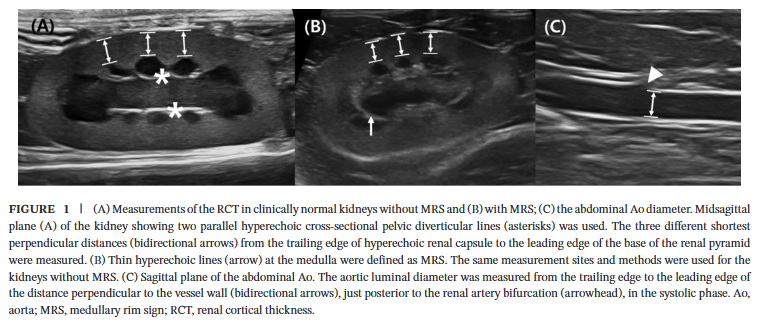

각 고양이의 보존된 신장 및 대동맥 초음파 영상에서 신장 피질 두께(RCT)와 대동맥 내경(Ao)을 측정하여 'RCT:Ao ratio'를 계산하고, 각 그룹 간의 통계적 유의성을 비교 분석하였습니다.

대동맥 측정위치

|